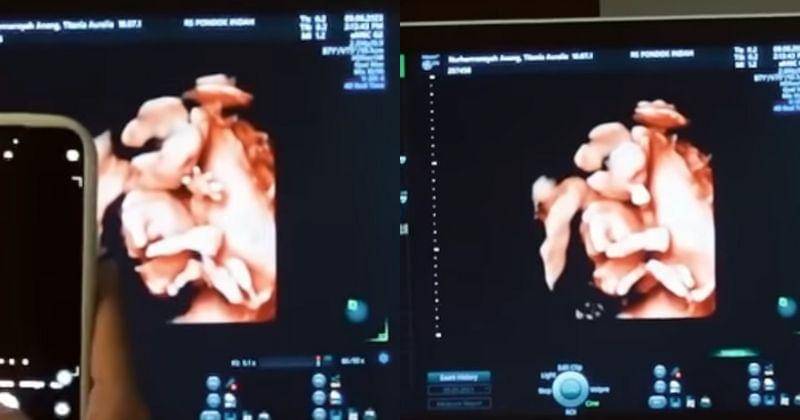

3. Sang janin membuka telapak tangan seolah sedang menyapa Papanya, gemas!

Salah satu hal yang paling menyenangkan dari periksa kandungan adalah saat melihat pose dan tingkah lucu janin ketika pemeriksaan USG. Janin seringkali memberikan momen gemas, seperti mengisap jempol, menendang, hingga membuka tangan.

Seperti yang ditunjukkan oleh calon anak kedua Aurel dan Atta ini. Saat semua orang sedang memerhatikannya dari layar monitor, tiba-tiba saja ia membuka tangannya seolah sedang menyapa dan melambaikan tangan.

Melihat tingkah bayinya tersebut, Atta langsung dibuat gemas. Ia pun langsung mengabadikan momen tersebut dengan memotretnya menggunakan kamera handphone.

4. Atta Halilintar menyebut bahwa sang bayi mirip dengan dirinya

Selanjutnya, dokter memperlihatkan lebih jelas wajah bayi yang dikandung Aurel. Melihat wajah bayinya, Atta Halilintar menyebut bahwa adik Ameena ini memiliki paras yang mirip dengan dirinya.

"Ini kok bentukannya kaya aku sih?" kata Atta sambil tertawa.